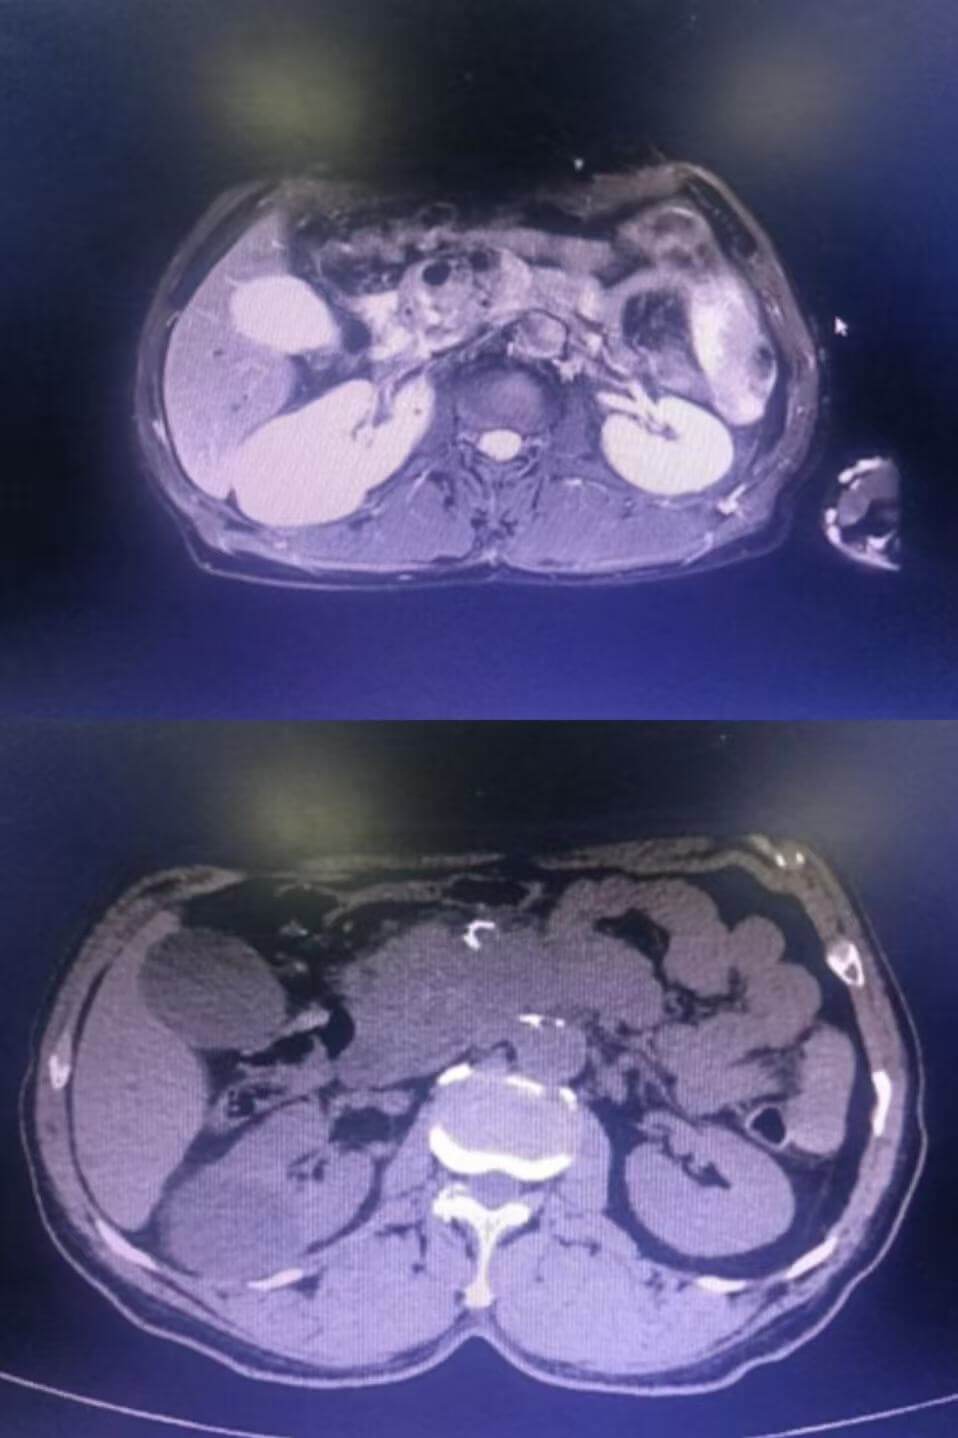

胰腺癌在腹部磁共振与腹部CT中的表现

当出现以下情况时,需警惕胰腺癌,尽早做腹部CT或MRI,必要时需要增强扫描或超声内镜进一步穿刺活检: